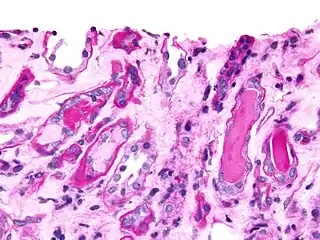

Bone marrow aspirate showing the histologic correlate of multiple myeloma under the microscope, H&E stain -

Plasmacytoma, H&E stain -

Atypical plasma cell infiltrate with both Russell (cytoplasmic) and Dutcher (nuclear) bodies (H&E, 50x)

Histopathology

A bone marrow biopsy is usually performed to estimate the percentage of bone marrow occupied by plasma cells. This percentage is used in the diagnostic criteria for myeloma. Immunohistochemistry (staining particular cell types using antibodies against surface proteins) can detect plasma cells that express immunoglobulin in the cytoplasm and occasionally on the cell surface; myeloma cells are often CD56, CD38, CD138, and CD319 positive and CD19, CD20, and CD45 negative.[15] Flow cytometry is often used to establish the clonal nature of the plasma cells, which will generally express only kappa or lambda light chain. Cytogenetics may also be performed in myeloma for prognostic purposes, including a myeloma-specific fluorescent in situ hybridization and virtual karyotype.

The plasma cells seen in multiple myeloma have several possible morphologies. First, they could have the appearance of a normal plasma cell, a large cell two or three times the size of a peripheral lymphocyte. Because they are actively producing antibodies, the Golgi apparatus typically produces a light-colored area adjacent to the nucleus, called a perinuclear halo. The single nucleus (with inside a single nucleolus with vesicular nuclear chromatin) is eccentric, displaced by an abundant cytoplasm. Other common morphologies seen, but which are not usual in normal plasma cells, include:

- Bizarre cells, which are multinucleated

- Mott cells, containing multiple clustered cytoplasmic droplets or other inclusions (sometimes confused with auer rods, commonly seen in myeloid blasts)

- Flame cells, having a fiery red cytoplasm[43][44]